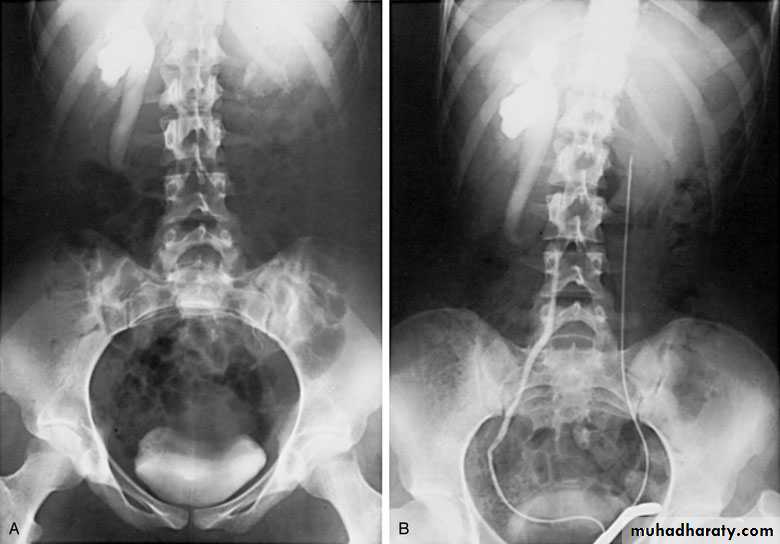

Ureteropelvic Junction (UPJ)(PUJ) Obstruction (stenosis)

The most common cause of significant dilation of the collecting system in the fetal kidney

Boys > Girls

Left-sided lesions predominate

15% bilateral

ETIOLOGY

Intraluminal : mucosal fold that causes valve

like effect.

Intrinsic (intramural) interruption in the

development of the circular musculature of the UPJ

Extrinsic An aberrant, accessory, or early-branching

SYMPTOMS/PRESENTATION

Most infants are asymptomatic and most children are discovered because of their symptoms

Episodic flank or upper abdominal pain, sometimes associated with nausea and vomiting

DIAGNOSIS

U/S: hydronephrosis

IVU: diagnostic , hydronephrosis with

fixed stenotic segment or complete

obstruction

CT scan: hydronephrosis that ends

abruptly